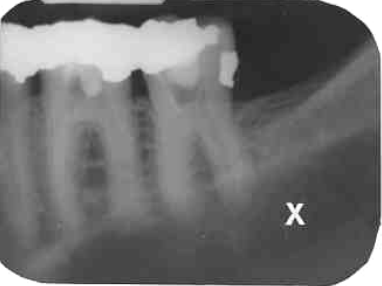

21. What is showing by X?